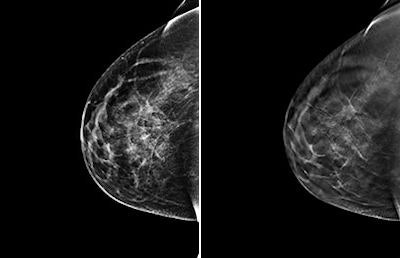

Left, 2D FFDM view of breast of 46-year-old woman. Right, 3D digital tomosynthesis view of breast. Images courtesy of Dr. Per Skaane, PhD.In fact, the combination of FFDM and tomosynthesis improved the cancer detection rate in women with a BI-RADS density measurement of 2, or minimal density, from 68% to 84% -- which could have interesting ramifications for clinical practice, according to Skaane.

The combination of FFDM and tomosynthesis had a cancer detection rate of 8.1 per 1,000 women, a 30% relative increase compared with FFDM alone, which had a rate of 6.1 per 1,000 women, the researchers found. In addition, the combination exam identified more cancers in denser tissue (BI-RADS 3 and 4) versus digital mammography alone: 80% versus 59%, respectively.